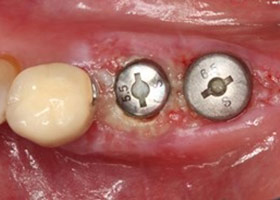

植牙後癒合狀況良好

假牙完成照

因植牙恢復正常咬合